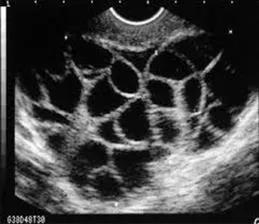

充满卵泡的卵巢

随之而来的潜在的风险就是OHSS。

患有OHSS的女性,可能会有不同程度的 腹胀、恶心、呕吐、腹泻、体质量快速增加、少尿或无尿、血液浓缩、血容量不足、电解质紊乱、胸腔积液、心包积液、腹腔积液、呼吸窘迫综合征,伴血栓形成倾向的高凝状态及多器官功能衰竭[2] 。

而且,增大的卵巢如果发生卵巢扭转或卵巢囊肿破裂、出血等并发症,必要时也要采取手术治疗,有可能影响女性的生育功能[3]。